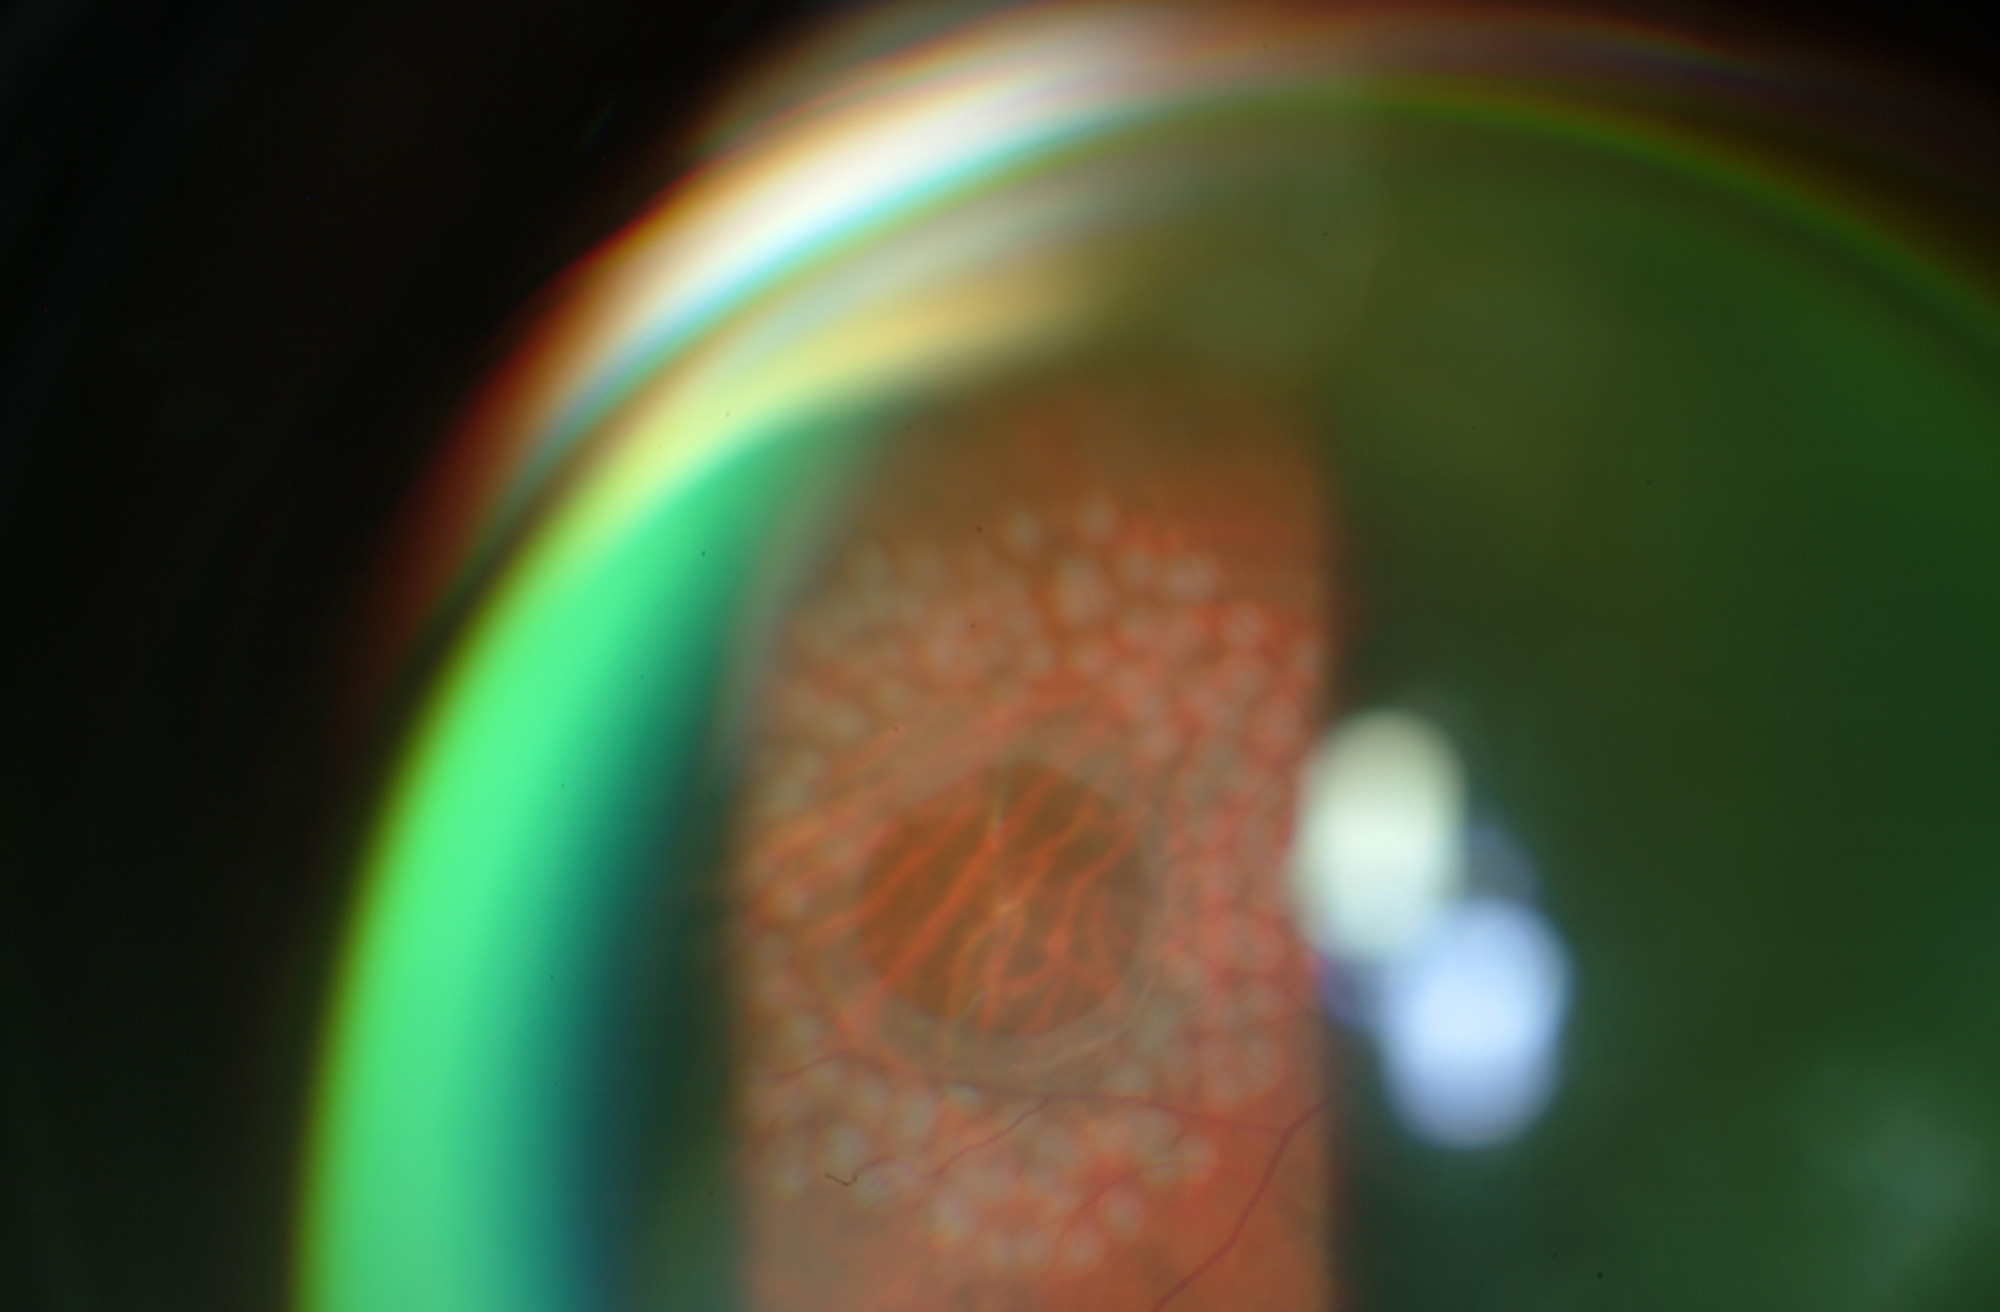

Consiste en producir una quemadura en la retina con el fin de sellar roturas, eliminar vasos sanguíneos anómalos y tratar zonas enfermas de la retina.

Consiste en la aplicación de unos impactos de láser en la cápsula posterior opacificada con el objetivo de realizar una abertura en la misma y mejorar la visión del paciente.